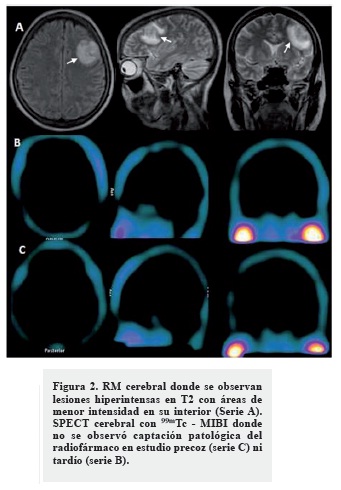

Al séptimo día del ingreso comenzó con crisis focales simples mioclónicas que involucraron el miembro superior derecho, lo que motivó una interconsulta con neurología. En el examen físico neurológico no se constataron signos focales ni papiledema. Se decidió realizar una TC cerebral donde se observaron múltiples lesiones en anillo (frontal izquierda, occipital derecha y parietal posterior derecha) asociadas a edema, que no desplazaron las estructuras de la línea media ni produjeron herniaciones, las cuales captaron poco contraste en la periferia en estudio de TC contrastada (Figura 1). Las características imagenológicas de estas lesiones ofrecían la duda diagnóstica entre una infiltración al sistema nervioso central por su enfermedad de base o múltiples abscesos cerebrales.

Decidimos realizar una SPECT cerebral con 99mTc - MIBI donde no se observó captación patológica del radiofármaco en el estudio precoz el ni tardío (Figuras 2, serie B y C). Ante la negatividad de este estudio, diagnosticamos que las lesiones evidenciadas en TC y RM de cráneo correspondían a abscesos cerebrales. La paciente fue tratada con antimicrobianos de amplio espectro y en estudio evolutivo a los 20 días -RM cerebral-, se observó una gran mejoría de las lesiones encefálicas (Figura 3).